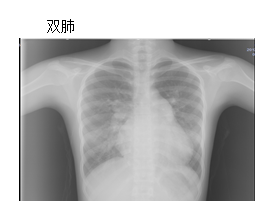

T 36.7℃,BP 左上肢100/60mmHg,氧饱和度99%;左下肢110/70mmHg,氧饱和度99%;右上肢90/60mmHg,氧饱和度99%;右下肢100/66mmHg,氧饱和度99%。神志清楚,口唇无紫绀。颈软,左乳腺区可见陈旧性手术瘢痕。双肺呼吸音清,未闻及干湿性罗音。心前区无隆起,未触及震颤,心界向右扩大,心率96bpm,心律齐,偶有早搏,1-2次/分。胸骨左缘第2-3肋间可闻及3/6级收缩期吹风样杂音,无传导。周围血管征阴性。双手无名指先天性手指畸形(短小)。双手中指、无名指、小拇指先天性无指甲畸形。 双侧肺血增多,肺无实变。气管无明确狭窄,双膈光整。二尖瓣型心,主动脉结小,肺动脉段凸,右下肺动脉干增宽,右心房、室增大,心胸比率:0.66。 心脏超声:房间隔中央部可见回声连续中断,缺损口径:3.8×3.5厘米,下腔静脉入口处残端纤细短小,长约0.6厘米,双期可见自左房流向右房的分流信号。 右心导管检查:肺动脉高压(轻度)